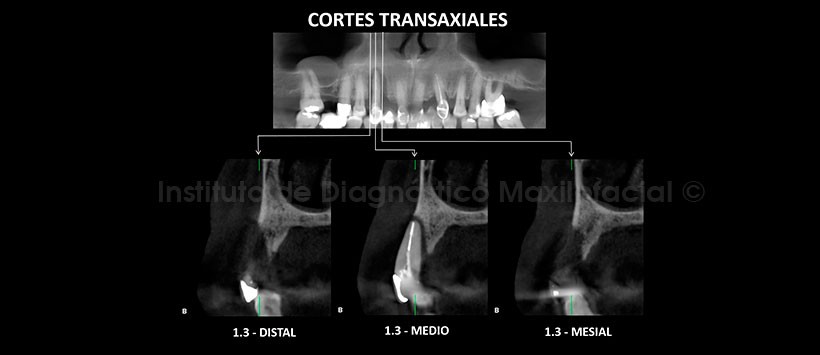

A la evaluación de la tomografía volumétrica (CBCT) en cortes axiales (Figura 2), transaxiales (Figura 3) y tangenciales (Figura 4), se evidencia reabsorción moderada del reborde dento-alveolar de la pieza 13 con presencia de defecto óseo peri-radicular de pieza dentaria 13 que ocasiona la pérdida de la tabla ósea vestibular.